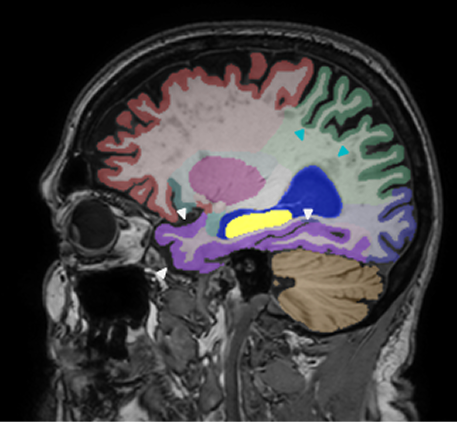

Retrospective brain volumetric analysis in a female patient diagnosed with Alzheimer’s disease at age 77 showed progressive brain atrophy over a 5-year period. The scans demonstrate temporal cortical atrophy with marked ex-vacuo enlargement of the lateral ventricles.

PATIENT

Female patient diagnosed with Alzheimer's Disease at Age 77

Analysis period

5 years

regions of interest

Temporal cortex

Hippocampus

Inferior lateral ventricles

Age 72

Age 74

Age 77

Lateral ventricle